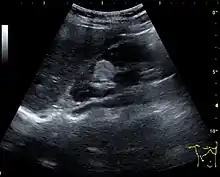

Figure 22. Chronic renal disease caused by glomerulonephritis with increased echogenicity and reduced cortical thickness. Measurement of kidney length on the US image is illustrated by ‘+’ and a dashed line.[1]

Figure 23. Nephrotic syndrome. Hyperechoic kidney without demarcation of cortex and medulla.[1]